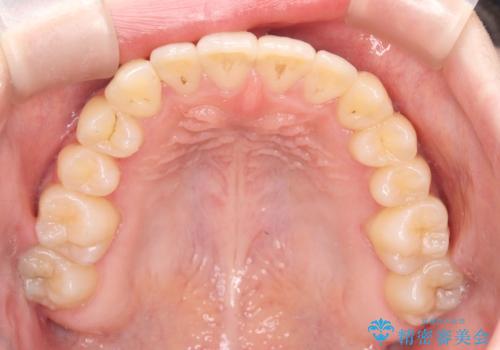

診査の結果、すでに下顎前歯の抜歯が行われていましたが、マウスピースの適合が著しく悪くなっており、歯が計画通りに動いていない状態でした。また、歯を支える骨の厚みや歯肉の薄さを考慮すると、このままマウスピースによる傾斜移動を続けるのは歯肉退縮(歯茎が下がること)のリスクが非常に高いと判断。

装置の変更と歯肉への配慮: ワイヤー矯正は歯の根(歯根)を平行に移動させる「歯体移動」を得意としています。本症例では、歯肉退縮を防ぐために、歯の傾きを精密にコントロールしながら抜歯スペースを閉じる必要がありました。ワイヤー装置を用いることで、インビザラインでは難しくなっていた三次元的な細かい調整を可能にしました。

リカバリーのプロセス: 適合が悪くなったインビザラインを一旦中止し、ブラケットを装着。停滞していた歯の移動を再開させ、上下の正中(中心)や奥歯の咬み合わせを一つひとつ整えていきました。